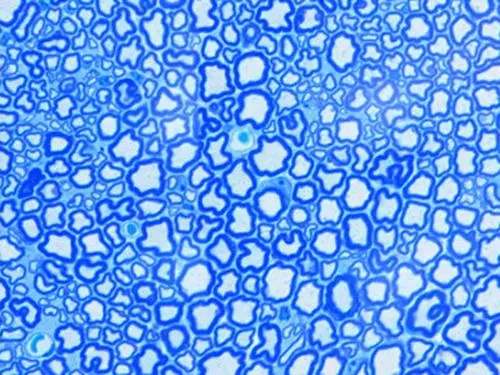

甲苯胺蓝染色

甲苯胺蓝染色:甲苯胺蓝是常用的人工合成染料的一种,属于醌亚胺染料类,这类染料一般含有两个发色团,一个是胺基,一个是醌型苯环,来构成色原显色。染料除有发色团外,还要有能使色原对组织及其他被染物产生亲和力的